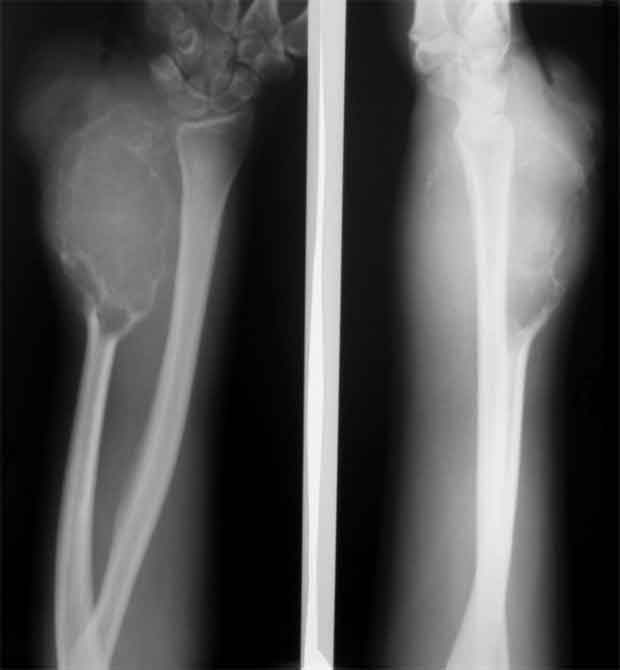

Re: остеобластеокластома локтевой кости

Уважаемые коллеги, госпитализировали, наконец, эту пациентку, чему не очень рады, как клиническая, так и рентгенологическая картины изменились, кроме того Hb 76.Направил на повторную консультацию к онкологу. Остеобластеокластома может себя так вести?